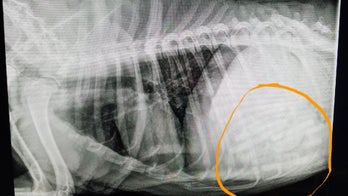

December 15, 2017 Oklahoma vet says he pulled 21 pacifiers from dog's stomach A veterinarian in Oklahoma took to Facebook last week to share what he described as “the most fascinating and exciting surgery” in his career.